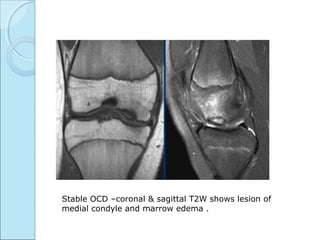

MRI CLASSIFICATION OF OCDMRI CLASSIFICATION OF OCD

 STABLE

* articular cartilage is breached.

*marrow edema.

Stable OCD –coronal & sagittal T2W shows lesion of

medial condyle and marrow edema .